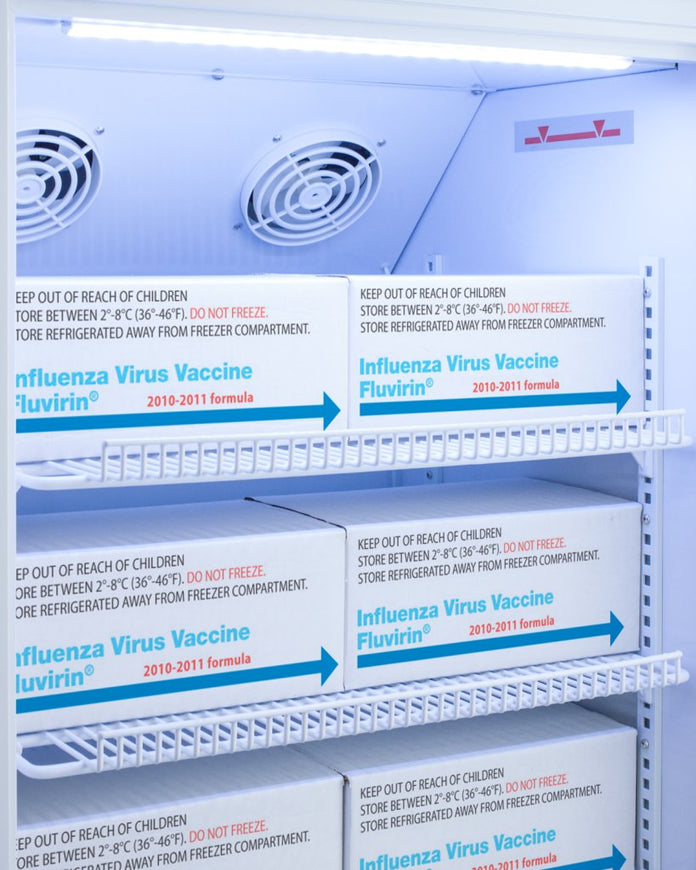

Controlled Room Temperature (CRT) cabinets are designed and purpose-built for ambient medication and vaccine storage in pharmacy and patient care areas

Shelf Type:Wire

Shelf Qty:7

Adjustable Shelves:Yes

Fan Type:Interior

Interior Light:Yes

Temperature Range:68 to 77F (preset to 72F)